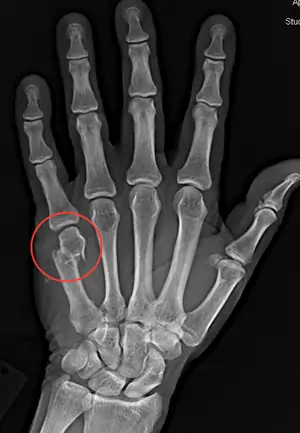

Scienza medica e pratica nei secoli hanno provato come l'utilizzo delle mani nude può portare a fratture (come la classica "frattura del pugile", una rottura delle ossa all'altezza del quinto metacarpo) ed a deformazioni delle mani, dislocazioni delle articolazioni e danni permanenti.